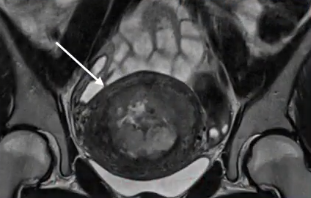

![]() |

| 轴位 T2 加权磁共振成像,中度信号强度 外生型宫颈肿块伴侵袭性病变 进入相邻的左侧半骨盆 | 轴位 T1 加权像显示有强化的向外突出的颈部肿块,该肿块已侵犯到邻近的左侧半椎体。 |

影像学检查结果:

T2 中等信号强度,会破坏T2低信号 深色的纤维性基质

可能为外生型、浸润型或宫颈内型(呈桶状)